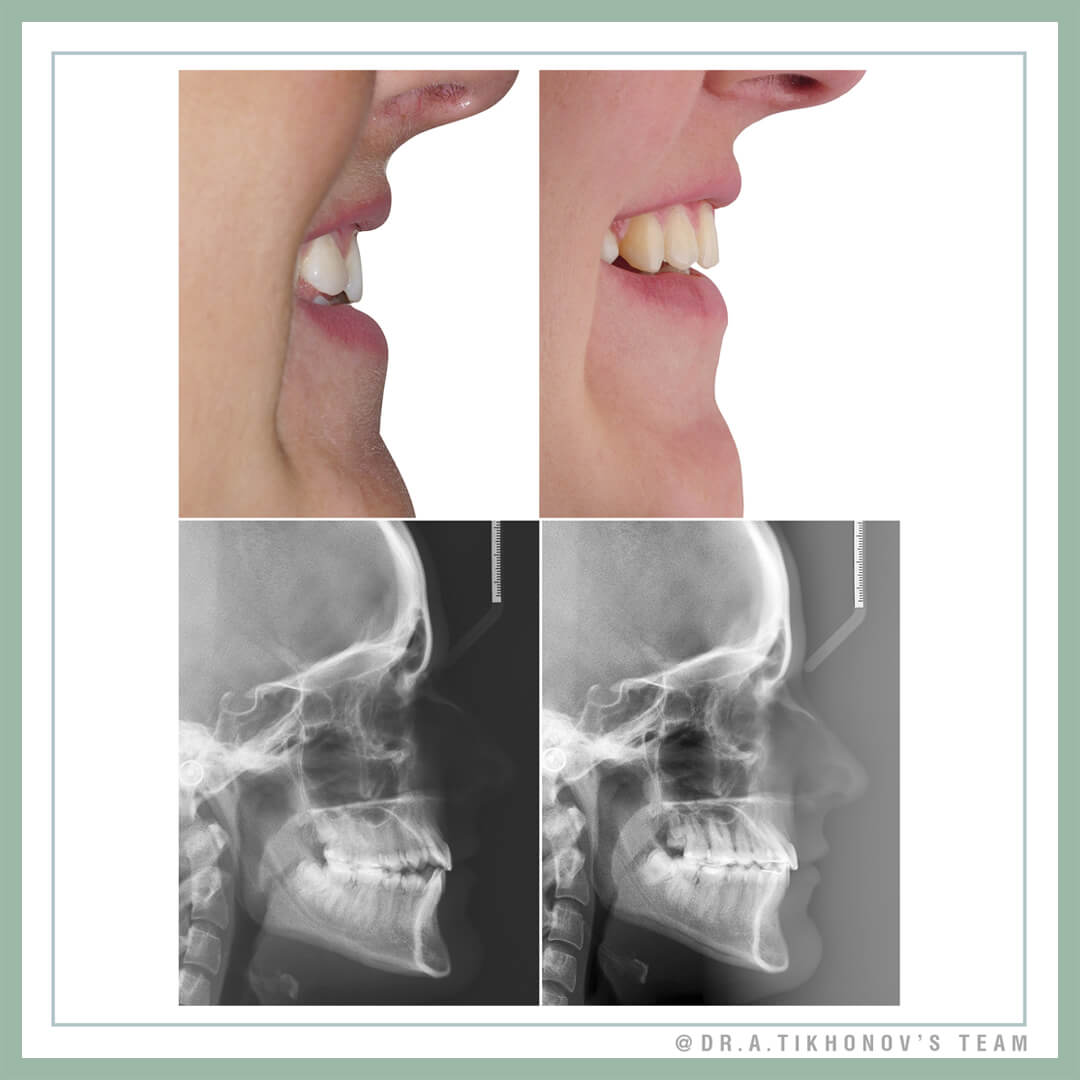

Посмотрите на первый слайд и подумайте как бы лечили своего близкого человека в такой ситуации, если жалоб на профиль нет. Остановите свой мозолистый большой палец и не листайте дальше, пока не ответите на этот вопрос. )Случай не простой, 3 класс, перекрестный, тенденция к открытому, адентия двух премоляров на верху. Сильная разница в ширине верха и низа. Симптомов ДВНЧС при этом нет.

Суммарный перекрест довольно значимый, вряд ли получится исправить его без скелетного расширения, что по традиционным представлениям все же пока еще SARPE.

The case is not so easy one, class III, cross bite, open bite tendency, huge difference between upper and lower transverse dimension. No TMJ problems.

I think, it’s not possible to fully correct cross bite without SARPE in traditional way (while MARPE in adults is still experimental option). If we try to correct by dentoalveolar movement, the molar roots will be out of bone or crowns should be tipped buccally with «hanging» palatal cusps and bite opening due to premature contacts. If we expand with SARPE, too much space will be created, that will lead to longer treatment to mesialize upper molars. The second option is to create space for Implants after expansion and distalization, that is also not perfect.